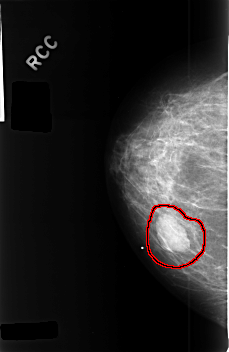

C_0404_1.RIGHT_CC

RIGHT_CC LINES 4576 PIXELS_PER_LINE 2968 BITS_PER_PIXEL 12 RESOLUTION 50 OVERLAY

FILE: C_0404_1.RIGHT_CC.OVERLAY

TOTAL_ABNORMALITIES 1

ABNORMALITY 1

LESION_TYPE MASS SHAPE OVAL MARGINS CIRCUMSCRIBED

ASSESSMENT 3

SUBTLETY 5

PATHOLOGY BENIGN

TOTAL_OUTLINES 1

BOUNDARY